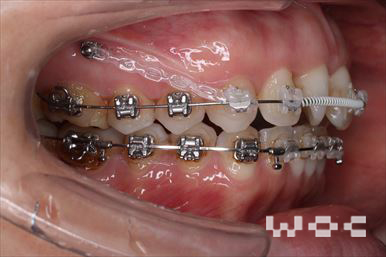

受け口・反対咬合エッジワイズ装置

特に装置の希望はなかったので、エッジワイズ装置を選択。

下顎両側臼歯部に歯科矯正用アンカースクリューを埋入し、下の歯列を後方へ移動しました。-

- 年齢:24歳女性

- 主訴:受け口を治したい

- 基本矯正料金:80万円

- 治療期間:1年3ヶ月

- 非抜歯